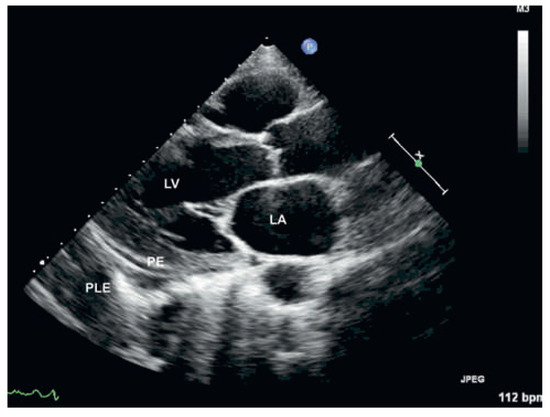

Early Versus Late Initial Echocardiographic Assessment in Infective Endocarditis: Similar Findings and No Difference in Clinical Outcome

by Nicole R. Bonetti, Mehdi Namdar, Huldrych F. Guenthard, Christiane Gruner, Matthias Greutmann, Jan Steffel, David Huerlimann, Christian Ruef, Felix C. Tanner, Rolf Jenni and Patric Biaggi

Cardiovasc. Med. 2012, 15(11), 317; https://doi.org/10.4414/cvm.2012.00115 - 21 Nov 2012

Background: The optimal timing of the initial echocardiographic assessment and the influence of microorganisms on echocardiographic findings in patients with infective endocarditis (IE) are not well studied. Methods: In 274 patients with IE, we studied the impact of antibiotic treatment duration of ≤2 days (early, 119 patients) or >2 days (late, 144 patients) prior to diagnostic echocardiography on IE specific findings and on clinical outcomes. Results were stratified for patients with Staphylococcus aureus (SA patients, n = 84) and those with other causative organisms (non-SA patients, n = 190). Results: There were no differences on specific echocardiographic findings between patients with early versus late echocardiography: Presence of vegetations: 91% vs 86%, p = 0.25; size of vegetations: 1.5 ± 0.7 cm vs. 1.5 ± 0.8 cm, p = 0.83; paravalvular abscess: 24% vs. 24%, p = 0.88, or valve destruction: 44% vs. 35%, p = 0.17. There were also no differences in terms of clinical outcomes between the two groups: Heart surgery for IE in 61% vs. 53%, p = 0.21, and in-hospital death in 8% vs. 11%, p = 0.46. The presence of SA was not associated with specific findings on echocardiography or worse clinical outcomes compared to non-SA patients. Conclusions: In patients with infective endocarditis, the findings of early vs late initial echocardiographic assessment did not differ, and echocardiographic findings did not allow inference on the causing organism. Neither the timing of the initial echocardiographic study nor any organism involved was associated with clinical outcome. Full article

Figure 1